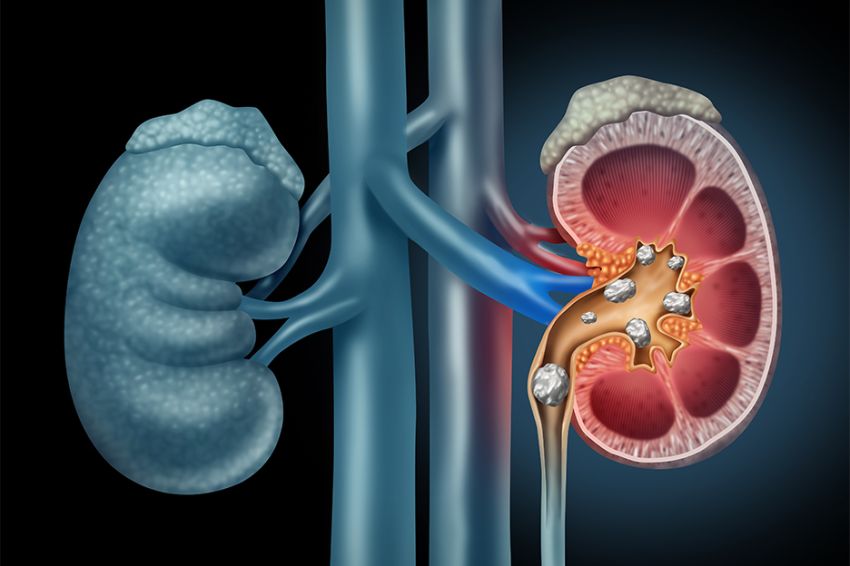

Menurut data Riset Kesehatan Dasar Nasional (Riskesdas) tahun 2020, prevalensi penyakit batu ginjal di Indonesia tercatat sebanyak 3.8% atau 739.208 jiwa. Foto Ilustrasi/iStock

Prof. Dr. dr. Nur Rasyid, SpU-K, Spesialis Urologi Siloam Hospitals ASRI menerangkan, penderita batu ginjal sendiri memang sering kali tidak merasakan gejala ataupun keluhan. Oleh sebab itu, tanpa disadari batu ginjal bisa menjadi besar.

“Beberapa gejala yang sering dirasakan oleh penderita batu ginjal yaitu nyeri pinggang yang hilang timbul meskipun tidak melakukan gerakan berlebih, kencing berwarna kemerahan atau kencing darah, kencing keruh berpasir atau keluar batu kecil, dan bila terjadi infeksi akan menyebabkan demam serta nyeri saat berkemih,” paparnya di Jakarta, Rabu (5/6/2024).

Prof. Nur menambahkan, seseorang akan berisiko lebih tinggi terkena batu ginjal jika salah satu anggota keluarga pernah menderita batu ginjal.

Faktor risiko lainnya yaitu dehidrasi atau tubuh kurang cairan. Apalagi bagi orang yang tinggal di iklim hangat dan kering sehingga mereka cenderung berkeringat dan malah banyak mengeluarkan cairan. Mengonsumsi makanan yang tingkat protein, natrium (garam), dan gula berlebihan juga dapat meningkatkan risiko beberapa jenis batu ginjal.

“Berikutnya, mereka yang obesitas, memiliki penyakit pencernaan, pernah melakukan prosedur pembedahan sebelumnya, atau kondisi medis lain seperti asidosis tubulus ginjal, sistinuria, hiperparatiroidisme, dan infeksi saluran kemih berulang, sering mengonsumsi suplemen dan obat-obatan tertentu, juga memperbesar risiko terjadinya batu ginjal ini,” jelas Prof. Nur.

Di Indonesia sendiri, metode perawatan terbaru untuk urologi di bidang batu ginjal yaitu Retrograde Intrarenal Surgery (RIRS). RIRS merupakan tindakan operasi tanpa bekas luka sehingga pasien yang menjalani prosedur ini bisa pulih lebih cepat dan melaksanakan aktivitas kembali secara normal.

Prof. Nur menjabarkan, pada dasarnya RIRS adalah prosedur penghancur batu ginjal dengan menggunakan laser. Sebelum dilakukan prosedur RIRS, pasien harus menjalani pemeriksaan laboratorium terlebih dulu, dilanjutkan pemeriksaan dengan CT scan.

Pemeriksaan menggunakan CT scan saat ini sudah mudah dijangkau dan menjadi standar pemeriksaan batu saluran kemih. Selain mengetahui letak dan ukuran batu, informasi tambahan penting adalah kekerasan batu dengan satuan HU (Hounsefield Unit).

”Dalam memilih prosedur RIRS, dokter akan mempertimbangkan faktor-faktor seperti ukuran dan jenis batu, serta kondisi kesehatan umum pasien. Informasi kekerasan batu mengubah algoritma dan anjuran dokter spesialis urologi dalam penanganan batu saluran kemih, di mana penggunaan ESWL (extracorporeal shock wave lithotripsy) semakin terbatas, karena batu dengan kekerasan lebih dari 1.000 HU tidak disarankan lagi, meskipun ukurannya tidak besar. RIRS dapat dilakukan pada batu ginjal berukuran kurang dari 3 cm, batu dengan kekerasan tinggi,” terangnya.